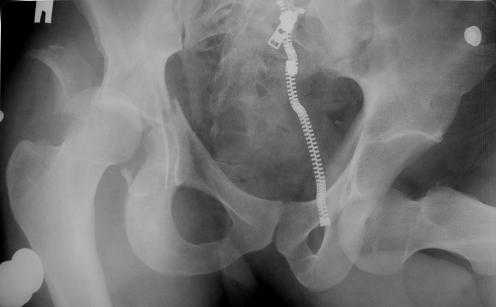

Уважаемые коллеги! Прошу посоветовать как лечить больного с двусторонним повреждением тазобедренных суставов. Пациент 30 лет поступил к нам в клинику по поводу закратого поперечного перелома свода, перелома задне -вехнего края правой вертлужной впадины, подвздошного вывиха правого бедра. Постравматического неврита правого седалищного нерва. Закрытого запирательного вывиха левого бедра. травма автодорожная 3 недели назад. Вправление вивихов при поступлении по месту жительства, получал скелетное вытяжение (слева в течении 2 недель).На контрольной Р-грамме обнаружена импрессия верхнего полюса головки левого бедра. Выполнено КТ.Планируем выполнить остеосинтез перелома правой ВВ наружным доступом.Подскажите пожалуйста, необходимо что либо предпринимать по поводу перелома головки левого бедра (в "Мюллере" описана костная пластика дефекта)? И как рано можно разрешить нагрузку на левую ногу.

Сегодня выполнил остеосинтез повреждения праовй ВВ из стандартного задне-наружного доступа: задний край - реконструктивной пластиной, поперечный перелом компрессирующим винтом. линия поперечного перелома распологается на уровне ямки вертлужной впадины, но задний край занимает не менее 30%.